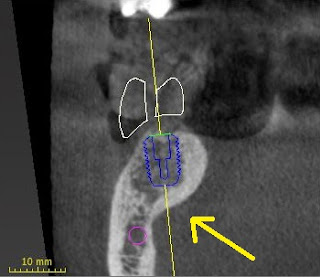

This latest blog will continue our discussion of using the latest CT digital imaging to plan and place dental implants. Today's implant placement software allows us to not only see if an implant can be placed prior to surgery, but after placing a digital implant in the software, we can translate that information to your actual mouth and have the implant placed precisely where it was in the software. This removes almost all risk in implant placement error. We also are excited to offer immediate implant placement following the same protocols. Frequently patients come in on emergency with fractured or decayed teeth that cannot be restored and unfortunately have to be removed. Immediate implants are dental implants placed the same day as taking the tooth out. This dramatically cuts down on healing time and can decrease overall costs. Prior to tooth removal, we can scan the mouth, digitally plan the case and have a custom guide fabricated for the day of surgery. Statistically there is little difference in success rates of immediate vs. delayed implant placement as long as you follow strict protocols and proper surgical technique! Here is an image of the treatment planning software with an implant placed in a healed site:

As you can see, I even custom fabricated a digital tooth, so I can place the implant in the best possible position to support the future crown.

This is what separates our surgical techniques from other offices whom may place implants freehand with out any CT data or guide. Our whole process and planning is based off the end result, a functional and aesthetic tooth.

By using precision guided placement, a surgical guide stent is fabricated with a sleeve that only allows placement in the location that was predetermined in the implant planning software. It is so accurate that the even the depth is predetermined and built into this surgical guide.